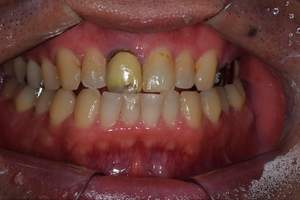

口腔内写真

- Befor

- After

| 年齢 | 50代・男性 |

| 主訴 | 左上7番 左下5番7番 |

| 治療内容 | ・インプラント埋入 ※1:GBR(骨造成)・・・骨再生誘導法。骨の高さや厚みを人工骨や人工膜などを使用し再生する方法 |

| 治療費 | 合計:1,809,500円(税込) ■内訳 ・左上7番 ・左下5番7番 |

| 治療期間 | 左上7番約1年 左下5番7番約10ヵ月 |

| 治療方針 | 左上7番は昔他院で被せものをしており、被せものの中が歯ぐきの中まで虫歯になっていたため抜歯せざるを得ない状態だった。抜歯と同時に骨造成を行い、骨が出来るまで4ヵ月待ってからインプラントを埋入した。 ※2ポンティック・・・歯のない部分を補うダミーの歯。 |

| 担当者所見 | 元々金属の被せものが多く入っていたため、2次カリエス※3が多かった。今回は金属ではなく、ジルコニアを使用し、2次カリエスにならないよう、患者様にはブラッシング指導とメンテナンスの重要性をお伝えした。 ※3二次カリエス・・・詰め物や被せものを入れた歯が虫歯になること。 |